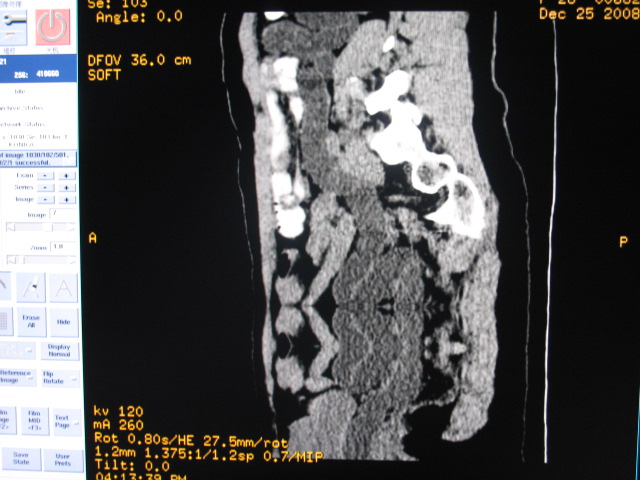

女,28岁,自觉腹部包块一年余

左侧为扩张的输尿管,一直延续到膀胱,那么它的上端应该是扩张的肾盂,但是在他的下方我们看到一个比较正常的肾,所以考虑左侧重复肾盂输尿管畸形。

考虑左侧双肾盂双输尿管畸形,其中一输尿管末端梗阻(不排除异位开口可能)并相应之肾盂及输尿管明显扩张积水。

考虑左侧双肾盂双输尿管畸形,其中一输尿管末端梗阻并输尿管肠管样扩张盂曲、肾盂囊状扩张积水。

术后证实是左侧双肾盂双输尿管畸形,巨输尿管巨肾盂症